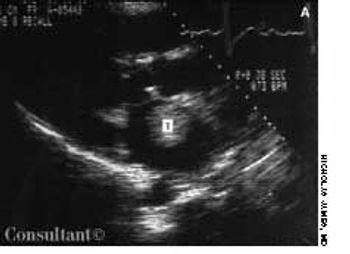

A 72-year-old man with a history of rheumatic heart disease presented with pulmonary congestion and syncope. Results of the cardiac examination suggested mitral stenosis and atrial fibrillation with a controlled ventricular response. Two-dimensional echocardi-ography revealed a large, free-floating ball thrombus (T) in the dilated left atrium and demonstrated rheumatic and severely stenotic mitral valve leaflets.